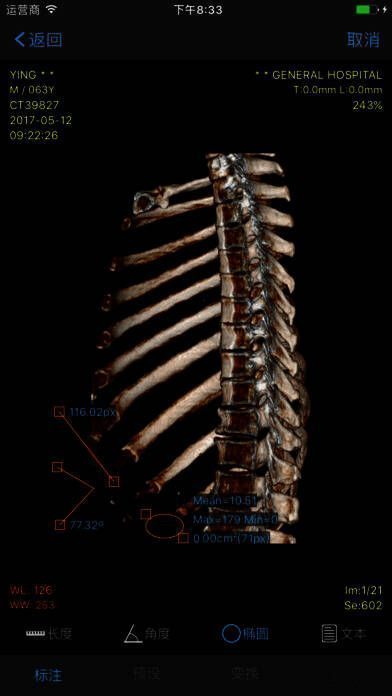

2. 多项功能,强大实用:可进行 WL、测量、角度、CT 值、旋转等操作。

- 多项功能,强大实用:可实现 WL、测量、角度、CT 值、旋转等操作。